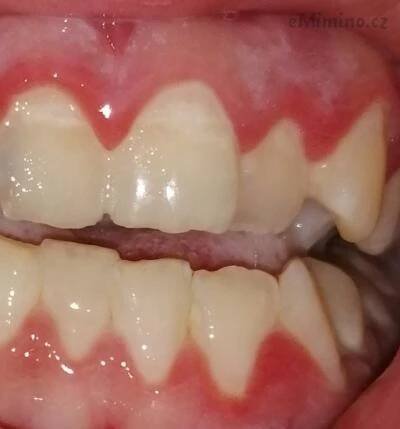

Jak rozpoznat paradentózu? - Léčba a správná péče

Zjistěte, jak poznat zánět dásní, kdy hrozí paradentóza a co pomáhá.